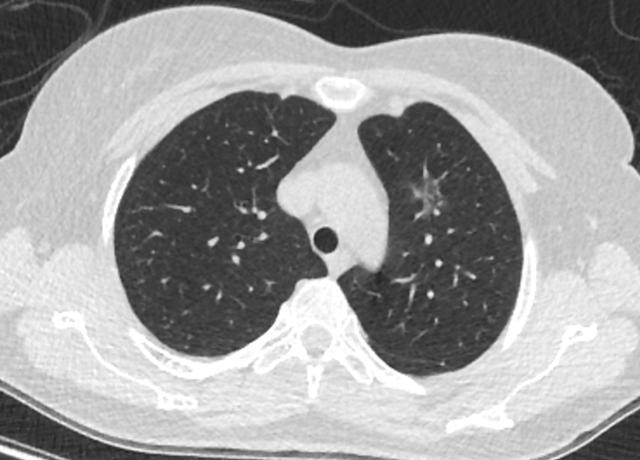

混合磨玻璃结节

多发的磨玻璃结节,慎重手术,因为病灶生长缓慢,我们不知道未来哪个结节先生长到威胁我们健康的时候,所以建议到了微浸润及以上,再根据病灶的生长位置,再决定如何手术,一次性手术切除几个病灶等,由胸外科和影像科共同做出规划。

不同阶段的多源发磨玻璃状肺腺癌